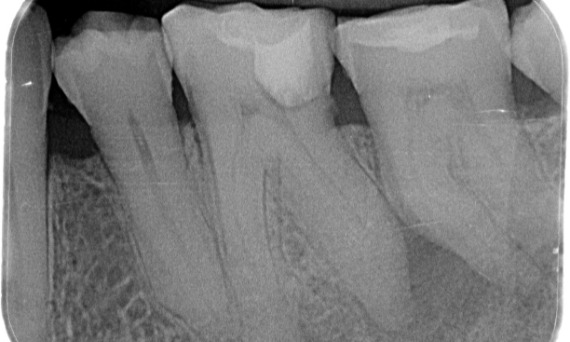

"I chose TruNatomy to be able to preserve as much dentin as possible to overcome occlusal load and increase the longevity of the tooth." - Dr. Abuelezz

Before: Upon examination, there was a caries lesion related to the lower right first molar. Radiographic examination revealed proximity of the lesion to the pulp horn and combining it with the chief complaint, a final diagnosis of chronic irreversible pulpitis was concluded.

After: Access cavity was done as conservative as possible. TruNatomy was the system of choice due to the young patient’s age. We needed to preserve dentine as much as possible to increase the tooth ability to overcome occlusal load and increase the longevity of the final restoration.

Cairo, Egypt